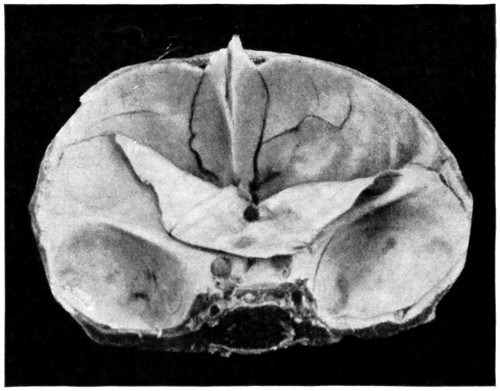

1. Occipital cephaloceles—the commonest variety—occupy, anatomically, two positions (1) between the two lower segments of the occipital bone (inferior occipital cephaloceles), often involving the foramen magnum and sometimes complicated by a condition of cervical spina bifida, and (2) between the two upper segments of the occipital bone (superior occipital cephaloceles), occasionally involving the posterior fontanelle.

Sincipital cephaloceles are usually quite small, but the occipital variety and those situated in[35] the region of the anterior fontanelle frequently attain a great size (see Figs. 20-22).

Fig. 22. An Occipital Cephalocele. (For further description, see text.)

The child was 3 months old, and presented a tumour, the size of an orange, situated between the occipital protuberance and the nape of the neck. The mass was pedunculated, the stalk being about the size of a four-shilling piece in diameter. It was soft, translucent, irreducible, and swelled up on coughing. An attempt at removal was carried out, and, after incising the outermost layers, three ounces of cerebro-spinal fluid escaped. A second tumour was then found occupying the base of the swelling. This was also punctured, more fluid escaping. Both sacs were cut away and the wound sewn up. Death occurred on the third day, preceded by convulsions, retraction of the head and neck, and high fever. The autopsy showed that the fontanelles were widely open, the anterior measuring 4 inches from side to side and 212 from before backwards. The bones of the vault were markedly thinned. In the subdural space there was a quantity of fluid, and the cerebral substance was soft and diffluent, the convolutions flattened, and the ventricles distended. There was a broad gap in the occipital bone, extending downwards into the foramen magnum, and in this situation the cerebellum had bulged backwards into the protruding mass. (See Fig. 22).